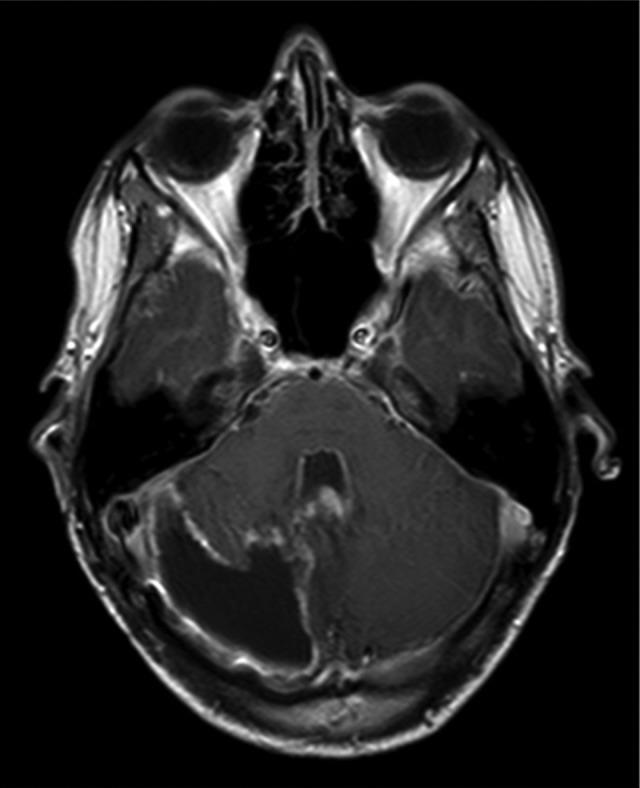

Pilocytic astrocytoma is a slowly growing neoplasia that represents the most frequent cerebral tumor in pediatric age. Malignant transformation is rare and it is usually related to previous radiotherapy. The authors describe a case of a spontaneous malignant transformation of a pilocytic astrocytoma. A 3-year-old boy was diagnosed with a cerebellar hemisphere tumor. He was submitted to a complete excision of the lesion, and histological findings were consistent with pilocytic astrocytoma. It was negative for p53. Twelve years later he presented with a local recurrence. Histopathological diagnosis was glioblastoma and it was positive for p53. Death from disease progression occurred 16 months after the diagnosis of glioblastoma. This case suggests that patients with pilocytic astrocytoma need closer follow-up and further genotypic studies in order to provide clues to clinical behavior. Such understanding can allow us to stratify treatment accordingly and to proceed to more aggressive treatment when necessary.

毛细胞型星形细胞瘤是一种生长缓慢的肿瘤,是儿童期最常见的脑肿瘤。恶性转化罕见,通常与先前的放疗有关。作者描述了一例毛细胞型星形细胞瘤自发恶性转化的病例。一名3岁男孩被诊断为小脑半球肿瘤。他接受了病变的完全切除,组织学检查结果符合毛细胞型星形细胞瘤。p53检测为阴性。12年后,他出现局部复发。组织病理学诊断为胶质母细胞瘤,p53检测为阳性。胶质母细胞瘤诊断16个月后,患者因疾病进展死亡。该病例表明,毛细胞型星形细胞瘤患者需要更密切的随访和进一步的基因分型研究,以便为临床行为提供线索。这样的了解可以使我们据此对治疗进行分层,并在必要时采取更积极的治疗措施。